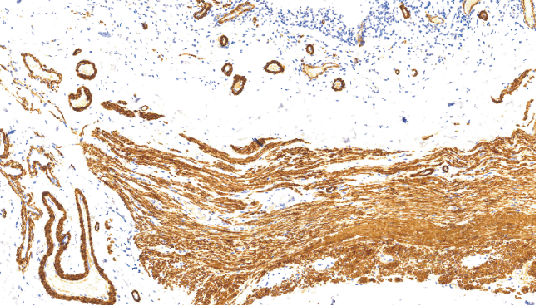

EpithelialMembrane Antigen(EMA)鼠抗人上皮膜抗原单克隆抗体

EMA是一组糖蛋白,广泛分布在各种正常上皮细胞膜上及其肿瘤中,分布范围与细胞角蛋白相似,但对内脏腺上皮的表达优于细胞角蛋白。因此对上皮源性肿瘤,尤其是低分化腺癌,最好与细胞角蛋白联合应用,可提高阳性率。EMA高温修复可增强染色强度

阳性部位:胞膜,胞质

适用组织:石蜡切片

预处理:热修复